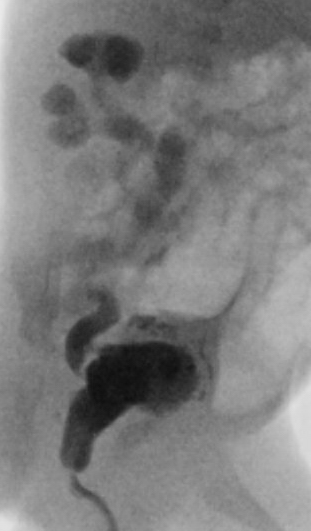

Links normale situatie: 1 nier, 2 nierbekken, 3 urineleider, 4 blaas, 5 overgang van urineleider in blaas, 6 plasbuis.

Rechts situatie zoals die bij urethrakleppen kan ontstaan: Verwijding van de nieren, het nierbekken en de urineleider. De urineleider wordt niet alleen wijder in de breedte maar ook in de lengte zodat en geslingerd verloop ontstaat. De blaas is zeer gespierd geworden en daardoor dikwandig en kartelig. De blaasuitgang is ook zeer gespierd en daardoor vernauwd. Het eerste deel van de plasbuis is verwijd tot aan de urethrakleppen. De blauwe pijl wijst naar de plaats van de urethrakleppen. Door de gespierde blaaswand wordt de urineleider die links in het plaatje zichtbaar is (dat is aan de rechter zijde van het kind) vernauwd waardoor de urineleider stroomopwaarts nóg meer verwijding vertoont. Aan de rechter zijde is de klep tussen urineleider en blaas beschadigd geraakt. De inmonding van de urineleider in de blaas is een wijde opening waardoor urine direct weer vanuit de blaas naar de nier kan stromen (Groene pijl)